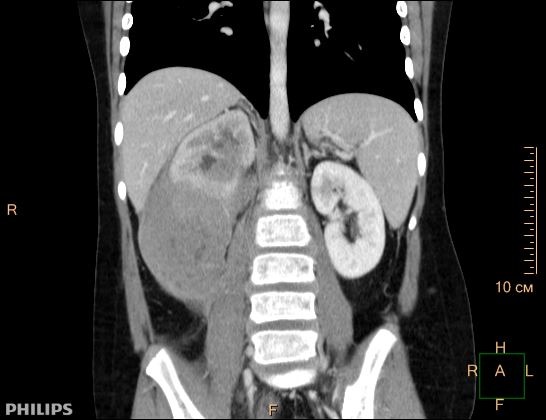

При локализации опухоли в животе у больного могут возникнуть тошнота, рвота, потеря аппетита, что быстро приводит к значительному снижению веса и обезвоживанию. Часто пациенты жалуются на боли в животе, а при осмотре определяется крупная, плотная опухоль больших размеров. Рис.1. Заболевание может проявляться кишечной непроходимостью, синдромом «острого живота», связанными с кровотечением, инвагинацией, перфорацией пораженной опухолью кишки, которые требуют немедленного квалифицированного хирургического лечения.

Рис. 1. Узловое образование правой почки, сливающееся с конгломератом увеличенных забрюшинных лимфатических узлов – специфическое поражение при лимфоме